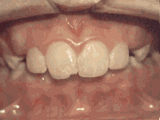

牙列拥挤,牙槽骨过窄,牙齿没有足够空间,只好前后左右高低上下乱长,经过矫正后的牙齿是这样的~